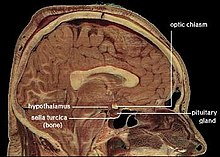

Cross-section of a human head, showing location of the hypothalamus.

For any animal, survival requires maintaining a variety of parameters of bodily state within a limited range of variation: these include temperature, water content, salt concentration in the bloodstream, blood glucose levels, blood oxygen level, and others.[93] The ability of an animal to regulate the internal environment of its body—the milieu intérieur, as the pioneering physiologist Claude Bernard called it—is known as homeostasis (Greek for "standing still").[94] Maintaining homeostasis is a crucial function of the brain. The basic principle that underlies homeostasis is negative feedback: any time a parameter diverges from its set-point, sensors generate an error signal that evokes a response that causes the parameter to shift back toward its optimum value.[93] (This principle is widely used in engineering, for example in the control of temperature using a thermostat.)

In vertebrates, the part of the brain that plays the greatest role is the hypothalamus, a small region at the base of the forebrain whose size does not reflect its complexity or the importance of its function.[93] The hypothalamus is a collection of small nuclei, most of which are involved in basic biological functions. Some of these functions relate to arousal or to social interactions such as sexuality, aggression, or maternal behaviors; but many of them relate to homeostasis. Several hypothalamic nuclei receive input from sensors located in the lining of blood vessels, conveying information about temperature, sodium level, glucose level, blood oxygen level, and other parameters. These hypothalamic nuclei send output signals to motor areas that can generate actions to rectify deficiencies. Some of the outputs also go to the pituitary gland, a tiny gland attached to the brain directly underneath the hypothalamus. The pituitary gland secretes hormones into the bloodstream, where they circulate throughout the body and induce changes in cellular activity.[95]